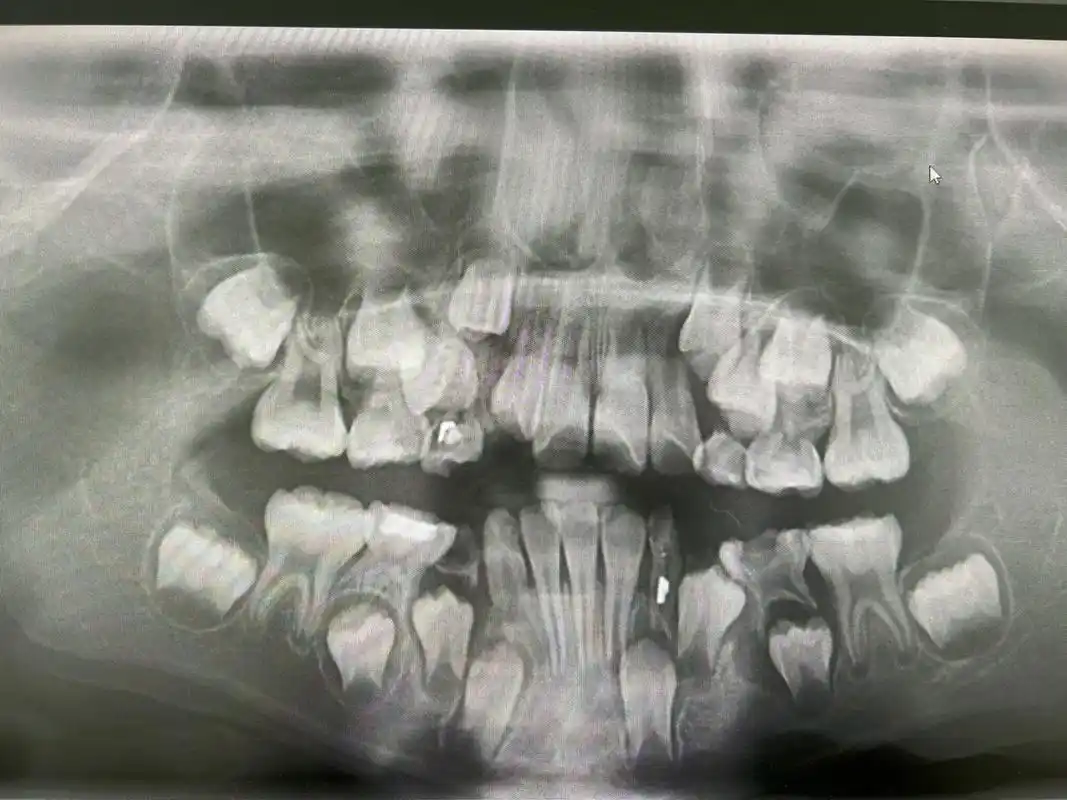

第一次见小朋友的牙片……真是满嘴牙

7周岁小朋友的牙片 我侄女刚拍的牙片,好多牙齿07

快来看看小孩子换牙期的牙片#牙片分析 #满脸都是牙 - 抖音

替牙期儿童拍摄全景牙片的意义这个孩子发现有多生牙和牙胚缺失

8岁儿童扩弓矫正 图一:牙片 有腺样体肥大,张口呼吸情况,6岁已手术

牙医接诊的儿童,家长说12岁了只换牙4颗,拍过片子后发现孩子牙齿多生